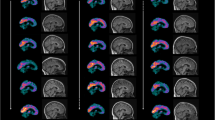

When present, cortical hypometabolism was lateralized in each lobe on individual patient analysis, resulting potentially in an underestimation of lateralized hypometabolism when confounding patients with different side predominance of hypometabolism. Therefore, we also performed separate SPM analysis in the group with left-sided predominant hypometabolism (n = 6) and in the group of patients with right-sided predominant hypometabolism (n = 3). In each of these groups, SPM analysis continued to show the posterior cingulate cortex (bilateral but predominant on the left side in the left-sided predominant group, and almost strictly unilateral on the right side in the right-sided predominant group) as the most hypometabolic area (Fig. 2). In the group with left-sided predominant hypometabolism, associated lateral and medial frontal and lateral parietal cortex hypometabolism involved larger areas extending into the lateral posterior temporal cortex (Fig. 2), whereas in the group with right-sided predominant hypometabolism only small zones of associated lateral frontal hypometabolism were seen (Fig. 2).

SPM analysis in the group with left-sided predominant hypometabolism (a–c) and in the group of patients with right-sided predominant hypometabolism (d–f) continued to show medial parietal cortex hypometabolism in both groups. In the group with left-sided predominant hypometabolism, associated lateral and medial frontal and lateral parietal cortex hypometabolism involves larger areas extending into the lateral posterior temporal cortex (a–c), whereas in the group with right-sided predominant hypometabolism only small zones of associated lateral frontal hypometabolism is seen (d–f)